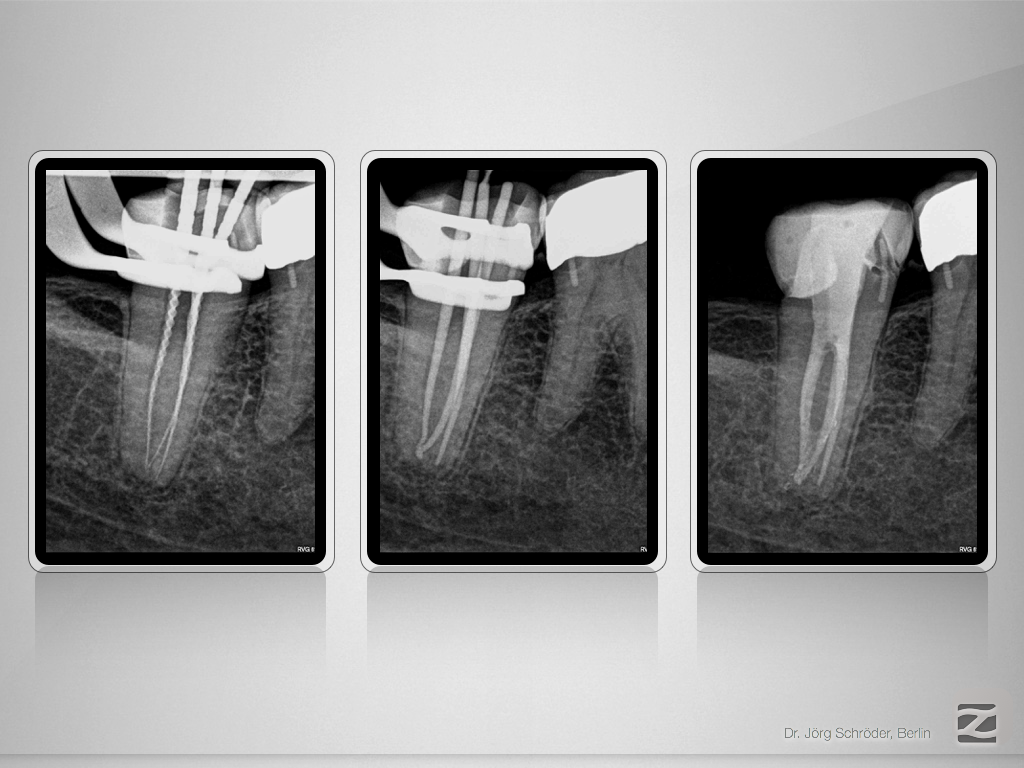

47d-011

„C“ ja – „C“ nein